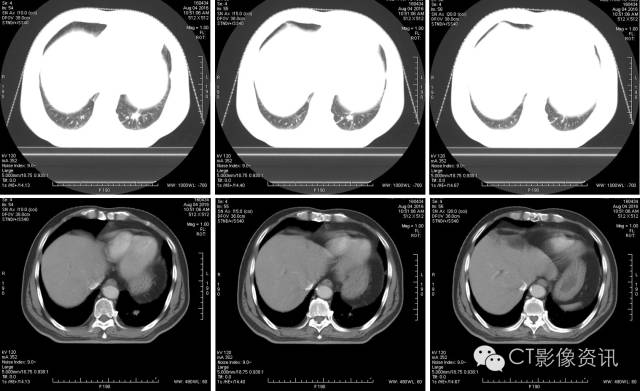

常规CT平扫

在肿瘤最大层面测量,最大径为15.2mm。

4D呼吸门控扫描

使用D4D呼吸门控扫描,可清楚观察到肿瘤本身随呼吸周期运动的情况。